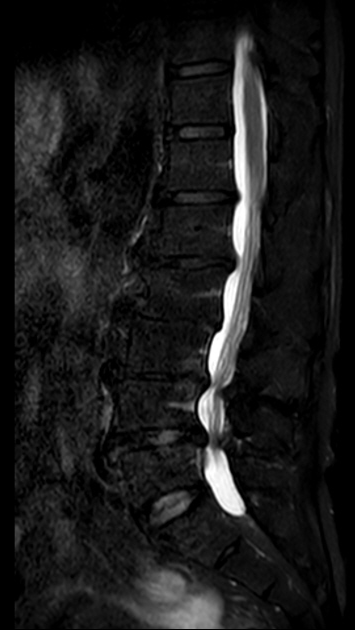

▲术前MRI

然而患者需行多节段腰椎融合

如何规避神经损伤风险?

64岁的邱某因“腰痛多年,加重伴左下肢放射痛1月”来到昆山市中医医院脊柱骨科陈勇主任门诊就诊,经对患者的评估后,陈勇主任考虑其为“腰椎间盘突出症、腰椎椎管狭窄症”,随即安排住院治疗。

入院后,陈勇主任在科室组织了病例讨论并表示:常规保守治疗只能缓解症状无法从根本上解决病根。目前,患者已保守治疗1月,症状未见明显缓解,且进行性加重。影像学可见腰椎间盘突出伴椎管狭窄严重程度高,有明确的手术指征,结合患者及其家属的意愿,选择腰椎后路减压植骨融合内固定术。